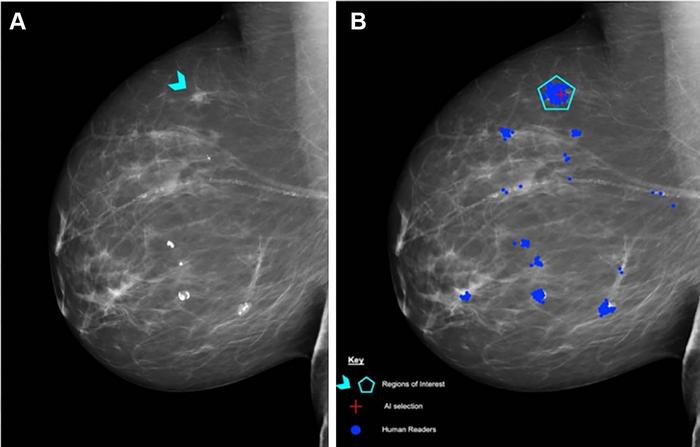

IMAGE: (A) RIGHT MEDIOLATERAL OBLIQUE UNADULTERATED MAMMOGRAM SHOWS AN 8-MM ILL-DEFINED MASS (ARROWHEAD), WHICH, AFTER BIOPSY, WAS DETERMINED TO BE A HISTOLOGIC GRADE 2 DUCTAL CARCINOMA OF NO SPECIAL TYPE. (B) MAMMOGRAM SHOWS FINDINGS BY HUMAN READERS (BLUE AREAS) AND THE LUNIT INSIGHT MMG ARTIFICIAL INTELLIGENCE (AI) ALGORITHM (RED CROSS). EACH BLUE DOT IS A MARK PLACED BY AN INDIVIDUAL HUMAN READER ON A PERCEIVED ABNORMALITY WHEN THE PERSONAL PERFORMANCE IN MAMMOGRAPHIC SCREENING (PERFORMS) CASE WAS READ. A REGION OF INTEREST (PENTAGON) HAS BEEN ANNOTATED BY THE PERFORMS SCHEME ORGANIZERS AND THEIR EXPERT RADIOLOGY PANEL. AI HAS CORRECTLY MARKED THE REGION OF INTEREST IN THE RIGHT BREAST FOR RECALL. SOURCE: PERFORMS VIA YAN CHEN. view more

Prof. Chen and her research team used test sets from the Personal Performance in Mammographic Screening, or PERFORMS, quality assurance assessment utilized by the UK’s National Health Service Breast Screening Program (NHSBSP), to compare the performance of human readers with AI. A single PERFORMS test consists of 60 challenging exams from the NHSBSP with abnormal, benign and normal findings. For each test mammogram, the reader’s score is compared to the ground truth of the AI results.

The research team used data from two consecutive PERFORMS test sets, or 120 screening mammograms, and the same two sets to evaluate the performance of the AI algorithm. The researchers compared the AI test scores with the scores of the 552 human readers, including 315 (57%) board-certified radiologists and 237 non-radiologist readers consisting of 206 radiographers and 31 breast clinicians.

No difference in performance was observed between AI and human readers in the detection of breast cancer in 120 exams. Human reader performance demonstrated mean 90% sensitivity and 76% specificity. AI was comparable in sensitivity (91%) and specificity (77%) compared to human readers.